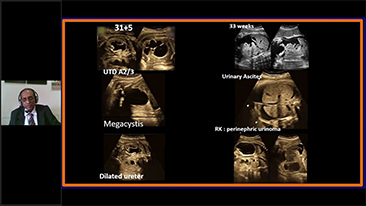

Geli?mi? ZST+ platformu ile desteklenen Nuewa'n?n tam kapsaml? ak?ll? ??zĂŒmleri, ?zellikle gebelik ?ncesi, gebelik ve do?um sonras? iyile?me sĂŒre?lerinde kad?n sa?l???n? iyile?tirmek, seviyeleri giderek daha da artan klinik zorluklar?n ĂŒstesinden gelmek i?in kapsaml? ve verimli tan?lar sunmak ĂŒzere tasarlanm??t?r.